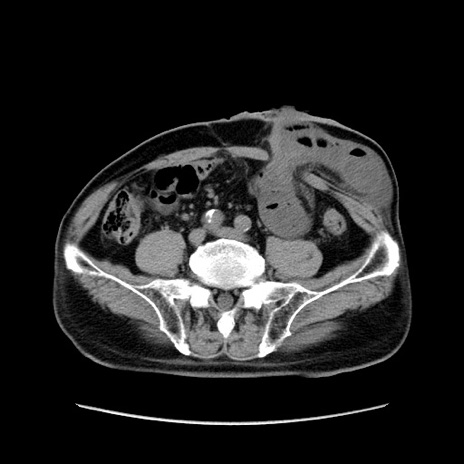

矢状断像